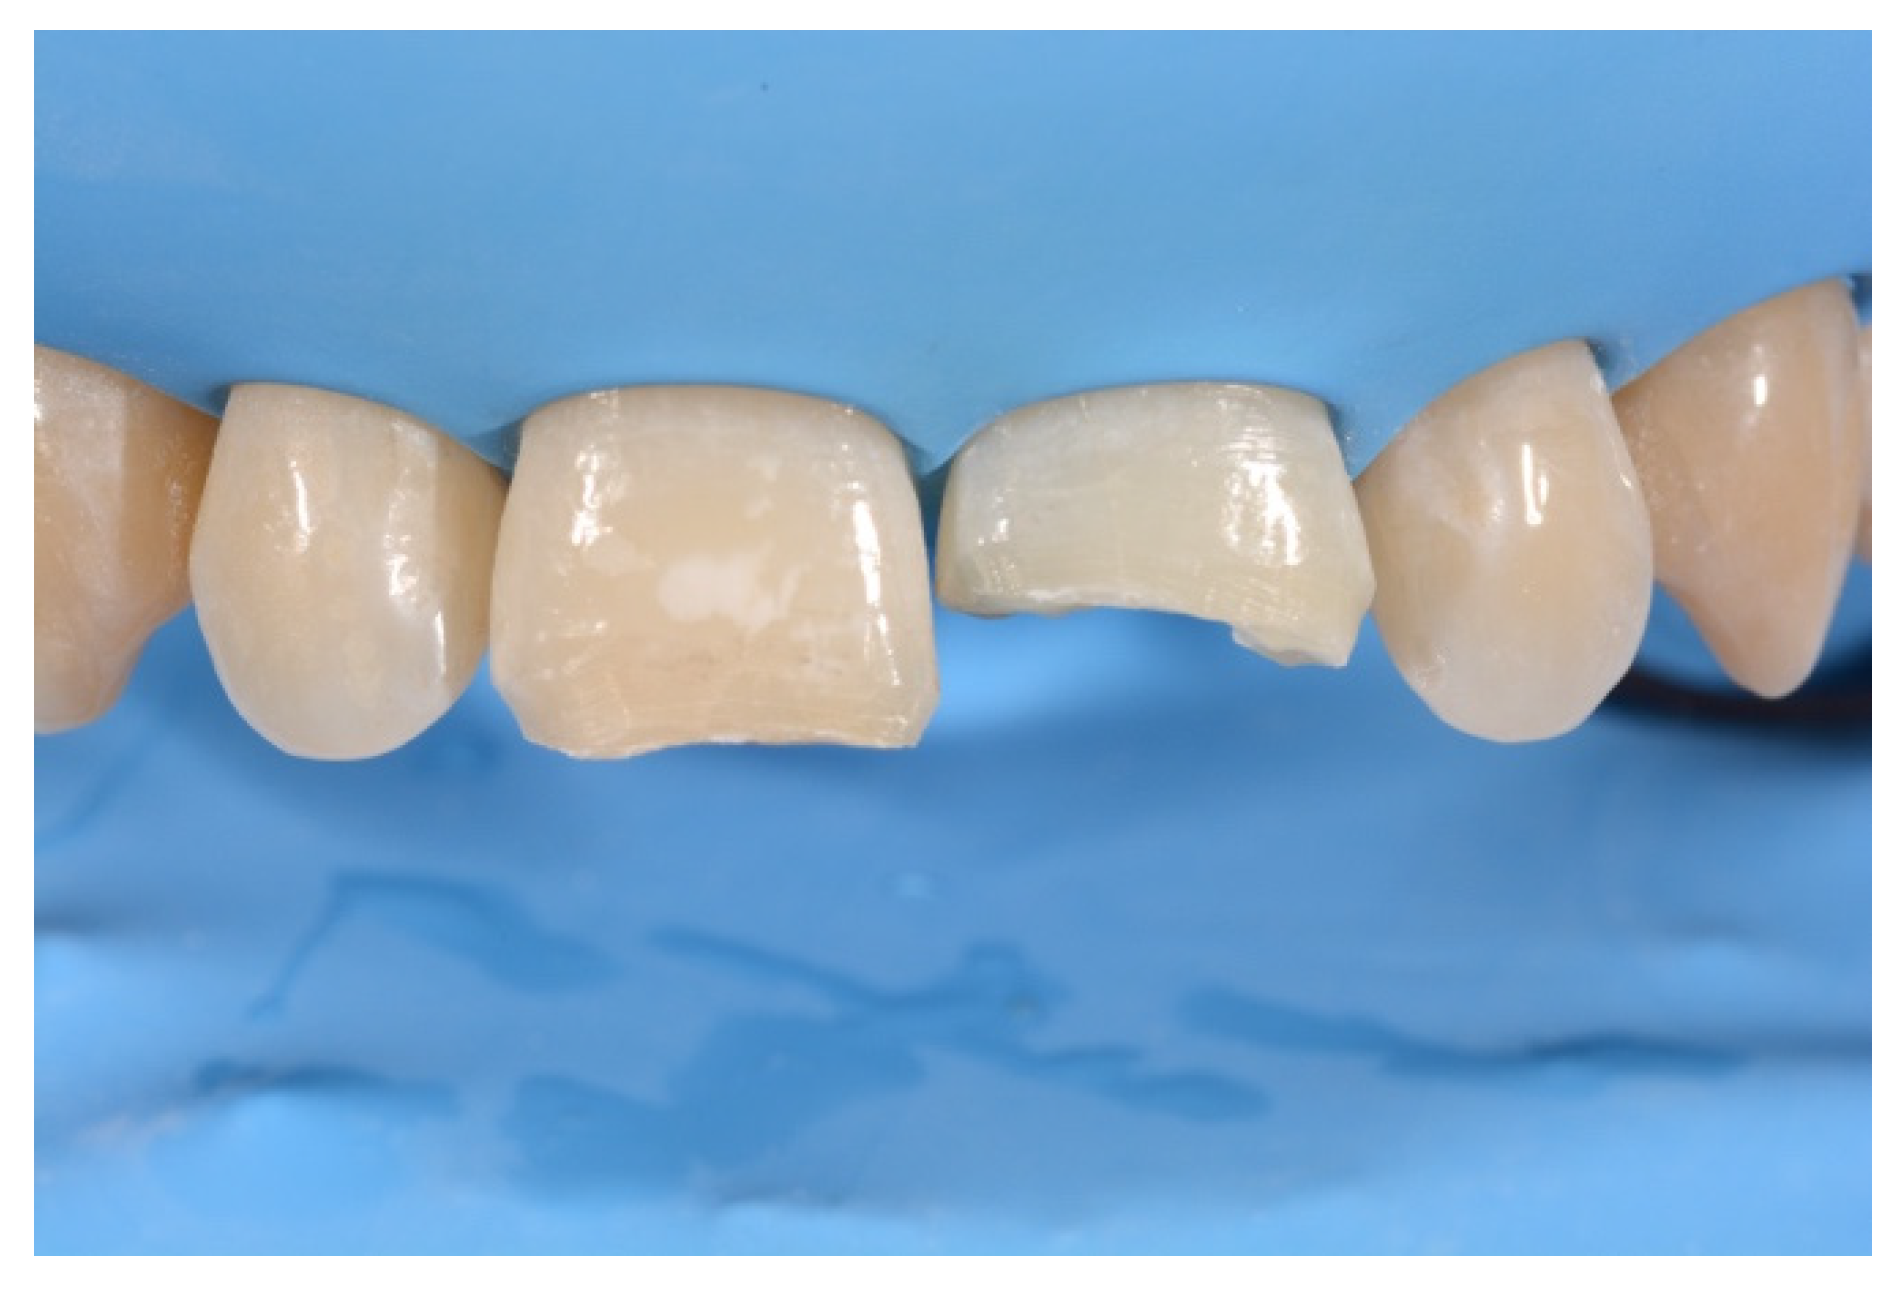

2. Case Presentation